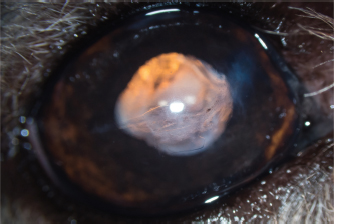

The responses to visual tests were positive on the left. The menace response was positive on the right, while the dazzle reflex was variable and difficult to interpret as a result of eye pain due to blepharospasm of moderate intensity. The left eye examination did not reveal any abnormalities. The right eye examination revealed the presence of sparse epiphora. A curvilinear, white, FB was present in the AC. Close examination with a biomicroscope revealed that it was a cat’s claw, for which the point of the corneal penetration was located in the upper quadrant. The latter was filled by a fibrin clot. Discrete corneal edema was present, as well as a uveal reaction manifested by tight myosis precluding observation of the lens (Fig. 1). The intraocular pressure was 7 mmHg, measured by rebound tonometry. Given the nature of the signs, FB extraction surgery was undertaken, associated with the perioperative exploration of the lens.

Fig. 1. Appearance of the eye at admission. Note the broken claw in the AC, corneal edema, fibrin clogging the entry point, and uveal reaction materialized by myosis.